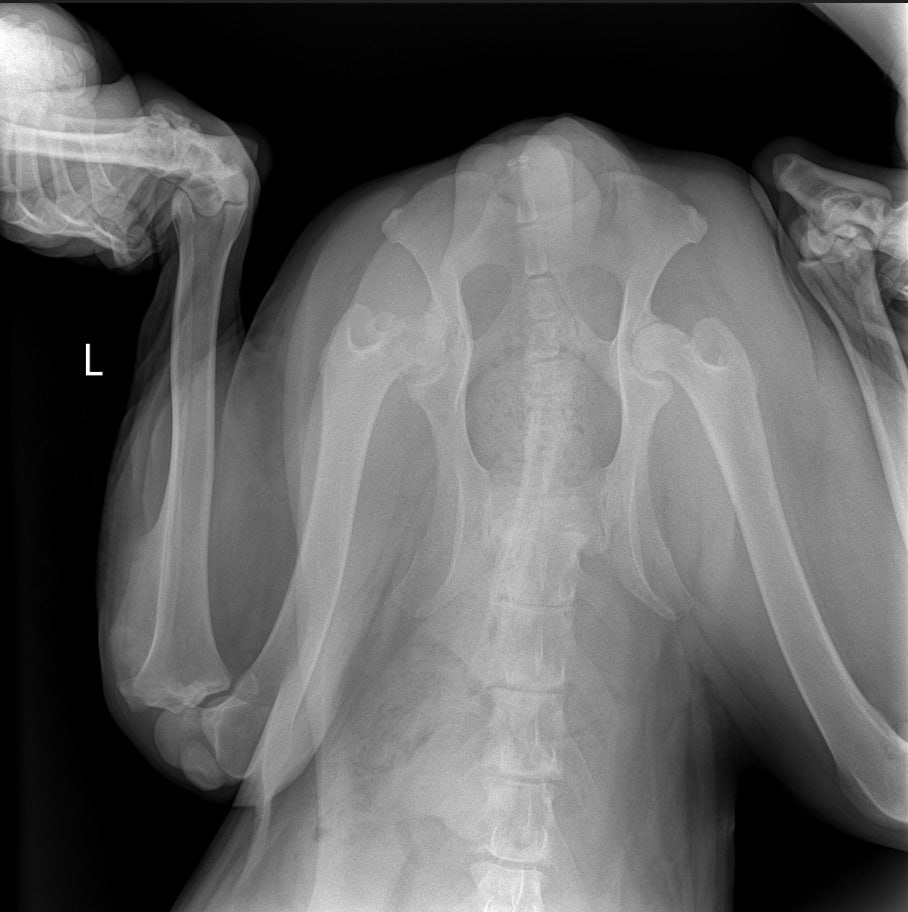

Рентген лапы, которая болит

Зона операции в снимок не попала....но со слов врача все нормально. То что видно - чисто....придется поверить, но так как шов подтекает, антиюиотик попробуем заменить на клиндомицин.

Сильнейший коксартроз тбс на больной лапе.....который не заметили на первичных осмотрах....зато настаивали в необходимости кастрации. В результате изменения положения лапы, нагрузки - воспаление и боль.